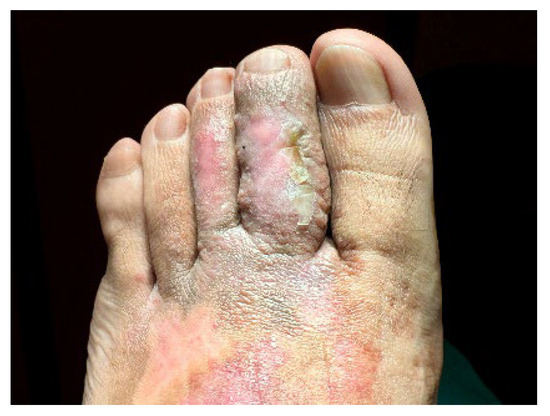

A 32-year-old healthy male presented with a brownish lesion on the dorsal surface of the left foot, evolving for 10 years. During this time the lesion progressively increased in size, involving the second, third, and fourth toes, and the medial border of the foot. Initially, the patient referred mild local pain, but in recent months developed mild pruritus. He denied systemic symptoms, mucosal involvement and similar lesions in other anatomical regions. He had no personal history of venous insufficiency, cardiovascular diseases or thromboembolic events. Physical examination revealed a brown plaque, with a focal erythematous hue, irregular borders, and ill-defined margins on the distal dorsum and medial border of the left foot. The lesion extended to the dorsal surface of the second, third, and fourth toes, here presenting with a thicker verrucous surface (Figure 1). Additionally, it extended towards the plantar surface of the distal and proximal/middle phalanges of the first and second toes, respectively (Figure 2). There were no palpable thrill or bruit and no oedema or varicous veins.

Figure 1. Brown plaque, with a focal erythematous hue, on the distal dorsum and medial border of the left foot, with a verrucous surface in the 2nd, 3rd, and 4th toes.